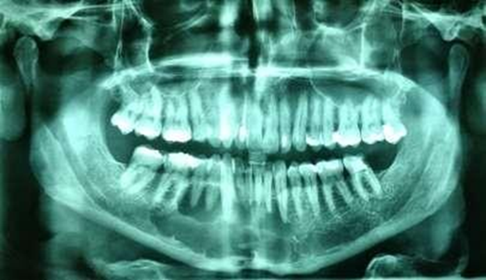

Figure 2. Initial panoramic

radiograph showing multilocular bone appearance

Upon clinical examination, an expansive

mandibular lesion was noted, the buccal bone plate presented slight crackling

and no teeth mobility was observed (Figure

1). Radiographic and tomographic examination (Figure 2 & Figure 3)

revealed an ill-defined multilocular radiolucency, with “honeycomb” aspect,

adjacent to the roots of the lower right canine and premolars, without

mandibular base involvement. Pulp vitality test was applied using endofrost

(cold) and gutta percha (heat), revealing vital canine and non-vital premolars.